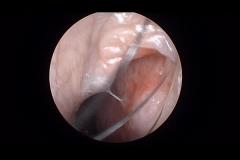

Frontal Sinus Case 2-15-2012

2/16/2012 12:23:28 PM

by Mac Barry

3326

1

0